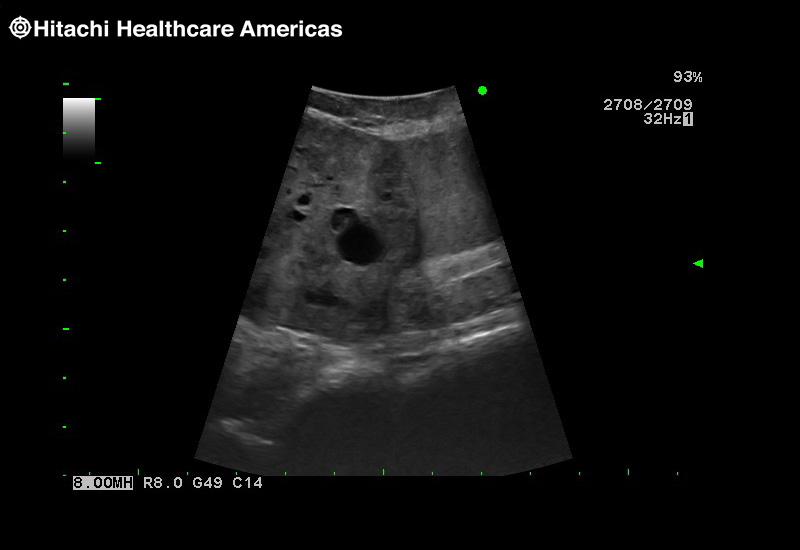

A critical function of robotic ultrasound guidance is tumor margin identification. Fujifilm's family of robotic probes all have the optimum location of the attaching mechanism that allows for full wrist articulation of the probe. The result is an increased confidence that the tumor margins have been completely identified.

The Arietta 65 has many advanced and unique probes that fully cover the expanding range of procedures that benefit from ultrasound guidance.

The Arietta 65 has many advanced and unique probes that fully cover the expanding range of procedures that benefit from ultrasound guidance.